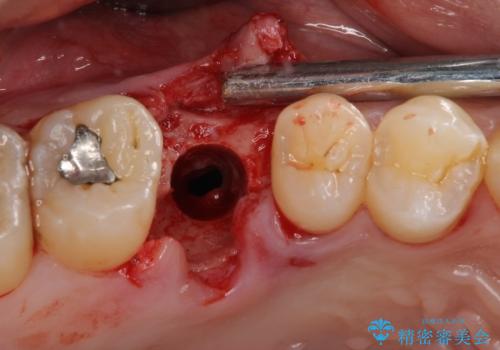

インプラント処置は、抜歯即時埋入を行い、十分な安定性が確認できたため、当日仮歯を装着しました。